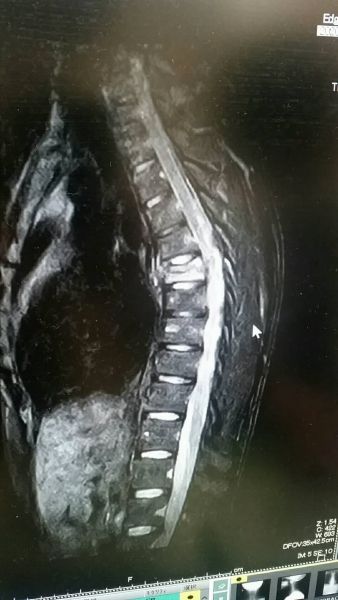

予定通り2月24日に退院させてもらいました(^^)ところがどっこい、まだまだ時間が掛かりそうです(T^T)白くなってるところが圧迫骨折の箇所です(´;ω;`)沢山の方に迷惑を掛けてしまって申し訳ないです(T^T)1日も早く復帰出来るように頑張ります!!!